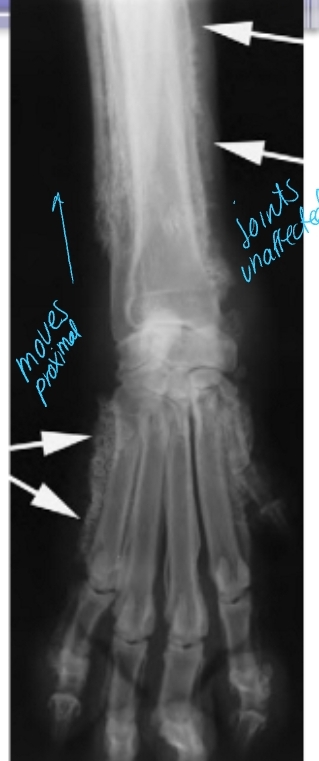

Hypertrophic Osteopathy (HO)

Et: Diffuse periosteal reaction, new bone formation around metacarpal/metatarsal/long bones (running up/down bone)

Paraneoplastic syndrome(lung tumor)

Path: Altered pulmonary function → increased blood flow → connective tissue congestion → periosteal bone formation

Sig: old dogs (rare in cats)

Cs: Reluctance to move, Swelling of distal extremities, Lethargy

Dt: Radiographs: affected limb/chest/abdomen

Uniform periosteal proliferation progressing proximally

Normal articular surfaces

Tx: Treat underlying disease